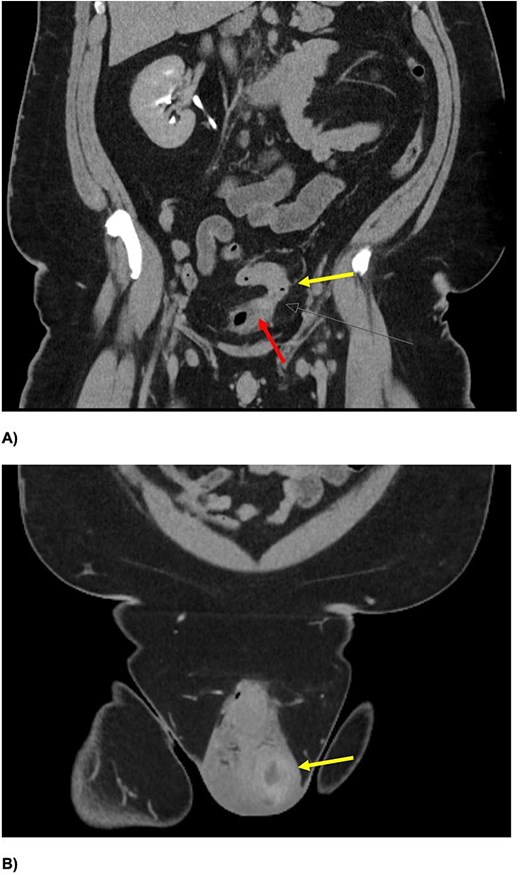

Inflammatory markers were mildly elevated—white cell count 12 × 109/l, C-reactive protein 30 mg/l. Scrotal ultrasound demonstrated a left intratesticular abscess, ruptured tunica albuginea, and suspected ischaemia (Fig. 1). Ordered due to recurrent AEO, a computed tomographic (CT) intravenous pyelogram revealed a fistula between the sigmoid colon and dome of the bladder, secondary to diverticular disease (Fig. 2). Urine cultures from his last admission for epididymo-orchitis grew multi-resistant Escheria coli and Enterococcus faecium.

Coronal slices of CT IVP (A) demonstrating a colovesical fistula between the inferior wall of the proximal sigmoid colon (yellow arrow (A)) and superior aspect of the urinary bladder (red arrow). There is intravesical gas with eccentric irregular anterior bladder wall thickening, and mild perivesical fat stranding. An enlarged left testis, with central hypodensity, and left testicular-scrotal abscess is also demonstrated (B).